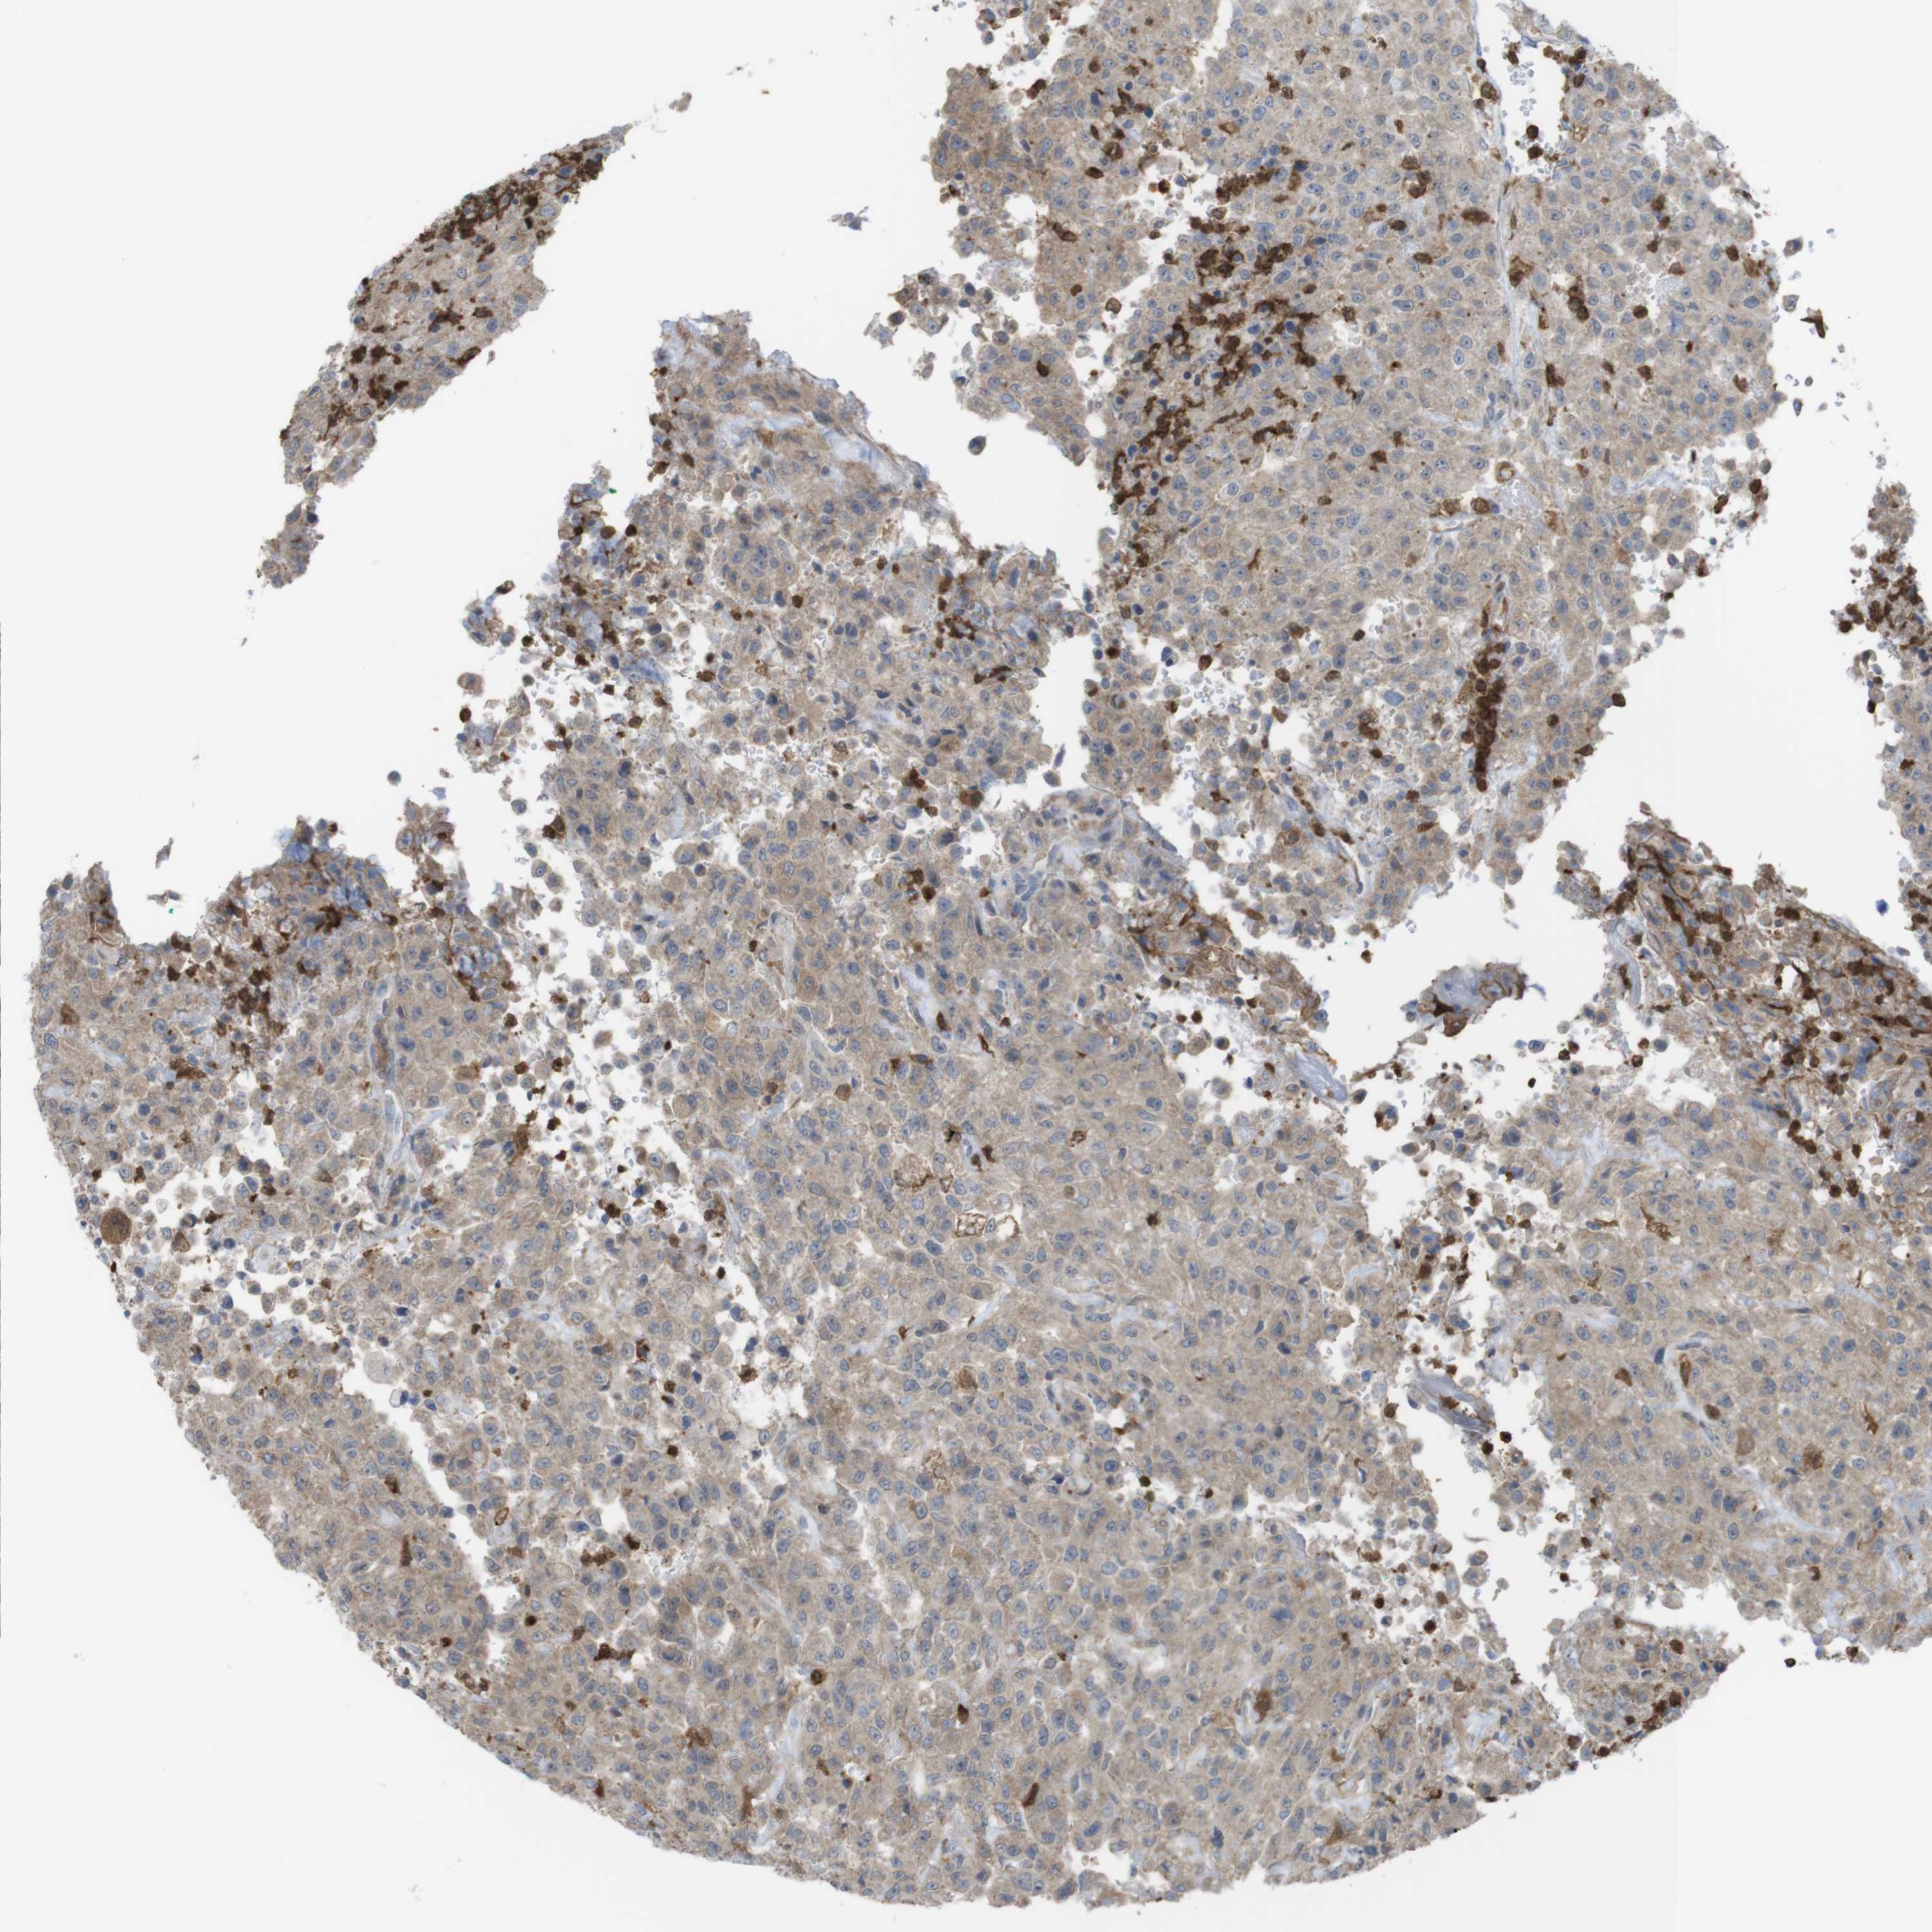

UROTHELIAL CANCER - Protein expressioni

A mouse-over function shows sample information and annotation data. Click on an image to view it in a full screen mode. Samples can be filtered based on level of antibody staining by selecting one or several of the following categories: high, medium, low and not detected. The assay and annotation is described here.

Antibody stainingi

Antibody staining in the annotated cell types in the current human tissue is reported as not detected, low, medium, or high, based on conventional immunohistochemistry profiling in selected tissues. This score is based on the combination of the staining intensity and fraction of stained cells.

Each image is clickable and will lead to virtual microscopy that enables deeper exploration of all samples and also displays staining intensity scores, fraction scores and subcellular localization as well as patient and tissue information for each sample.

Antibody HPA001863

Antibody HPA001890

Antibody CAB010469

Antibody CAB013225

Staining

High

Medium

Low

Not detected

Intensity

Strong

Moderate

Weak

Negative

Quantity

>75%

75%-25%

<25%

None

Location

Nuclear

Cytoplasmic/membranous

Cytoplasmic/membranous,nuclear

Urothelial carcinoma, High grade

Urothelial carcinoma, Low grade

Adenocarcinoma, NOS